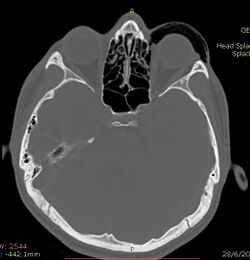

Computed tomography (CT)

CT scan taken from the transverse plane demonstrating orbital emphysema.[39]

Computed tomography is effective and sensitive in the diagnosis of orbital emphysema,[3][37] as it can confirm the anatomical location and size of air, bony defects, indentation of the eyeball, and the condition of the optic nerve, as well as the presence of any extraocular muscle entrapment and herniation of preorbital fat into the sinus cavities.[3][15][38] The location of the orbital emphysema is present near the site of the fracture.[1][3] The scans are usually taken along the transverse plane. Transverse images allow the evaluation of fractures in medial and lateral orbital walls. By reformatting these transverse images or taking coronal images, the examination of orbital floor and roof is permitted. Helical scanning is preferred as it has a lower imaging time and radiation dose comparing to conventional scanning, especially when reforming transverse helical scans into coronal images.[3] The staging of orbital emphysema can then be determined with visual acuity examination and ophthalmoscopy.[6] A disadvantage of using a CT scan is that when detecting air after orbital trauma, the presence of a wooden foreign object can give a false positive result of orbital emphysema. The wooden object can mimic the presence of orbital emphysema. Therefore, patients’ medical history is crucial in making the correct diagnosis.[3]